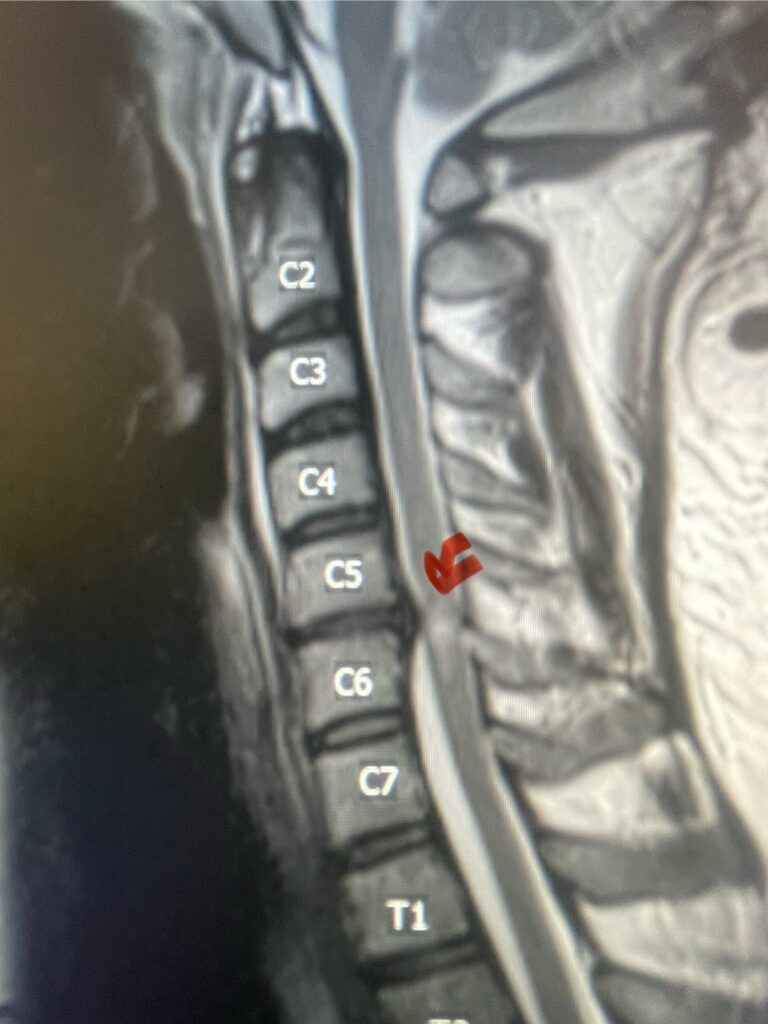

Fig 4: Sagittal T2-weighted cervical MRI demonstrating a significant disc osteophyte complex causing spinal cord compression at C 5 6 with extensive myelomalacia (red arrow)

A 37-year-old male police officer complained of a one-month history of difficulty with his balance and leg weakness. He complained of achiness in his legs. He also complained of bilateral arm weakness and numbness of his hands. He was also having difficulty writing due to the weakness. Patient had an MRI of the cervical spine which demonstrated a disc/osteophyte at C56 causing spinal cord compression and concurrent myelomalacia (Fig. 3). Patient underwent an anterior cervical discectomy with a cage and plate (Fig. 4). He tolerated the procedure well with improved numbness and weakness. This is a young person with fairly extensive myelomalacia and a fairly rapid development of symptoms. For this it was felt surgery was indicated. How he will do will depend on how much of his symptoms was caused by the compressive component or intrinsic damage to the spinal cord. As a rule, patients generally improve to some extent quickly; but their recovery of their spinal cord function can sometimes take up to 2 years to realize the extent of their improvement. Patients have to be patient with themselves in terms of their expected recovery.

Fig. 3: Sagittal T2-weighted cervical MRI demonstrating a significant disc osteophyte complex causing spinal cord compression at C 5 6 with extensive myelomalacia (red arrow)